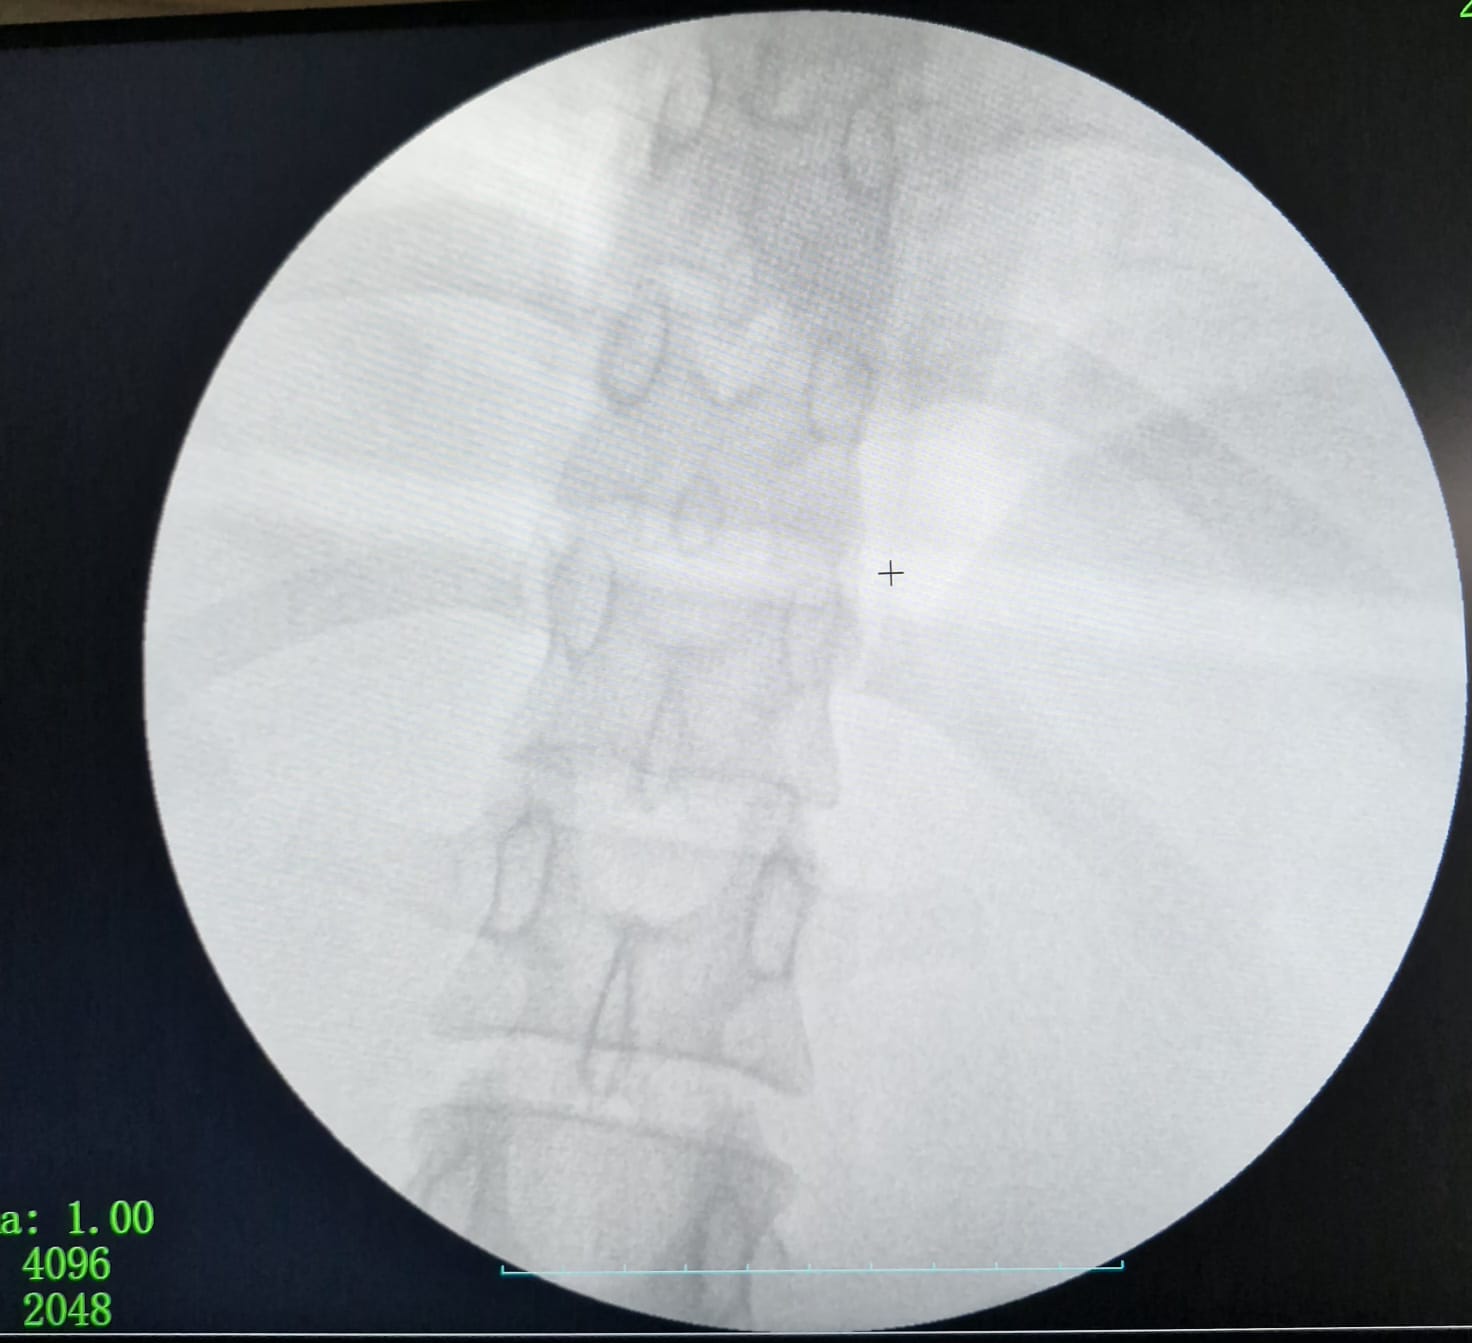

وأجرى الفريق الطبي العملية باستخدام المنظار عبر 3 فتحات صغيرة، مع الاستعانة بجهاز الأشعة (C-Arm) لتحديد موقع الإبرة بدقة، بدلاً من الجراحة التقليدية (فتح البطن)، ما ساهم في تقليل التدخل الجراحي وتسريع التعافي.